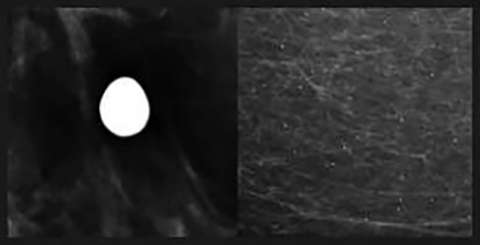

![]() Rim Calcifications: Include the previously described “eggshell” and “radiolucent centered” calcifications. These correspond to calcifications along round lesions such as oil cysts or simple cysts. These are usually associated with history of trauma or surgery.

![]() Milk of Calcium Calcifications: Craniocaudal View

![]() Milk of Calcium Calcifications: True Lateral Views